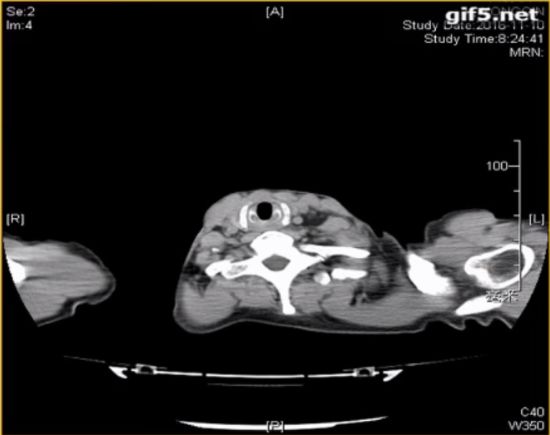

◆颈部CT

咽部及主支气管颈段异物,双侧颈部软组织间隙及胸壁皮下积气,气管破裂可能